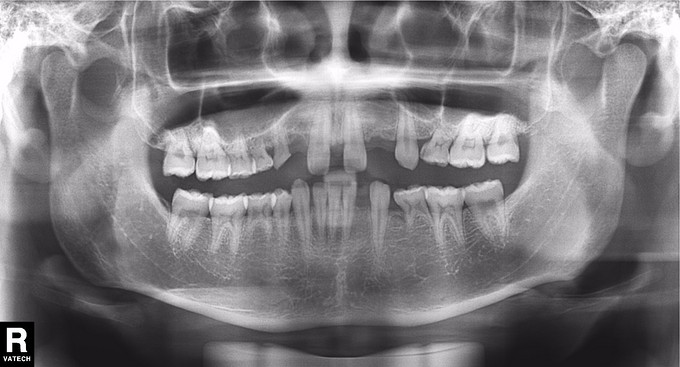

男 年龄16岁 右上恒牙2、3、4、5缺失,乳牙2、3、4、5滞留。 右下恒牙5缺失,乳牙5滞留。 左上恒牙2、3、4、5缺失,乳牙2、3、5滞留。 左下恒牙2、4、5缺失,乳牙2、5滞留。 诊断:恒牙先天缺失 治疗计划:a.乳牙治疗 b.唇系带手术 c.正畸治疗 d.种植体修复 现已经a、b两项治疗完成;因正畸难度较大,需要专家会诊共同完成!正畸治疗后再行种植修复。